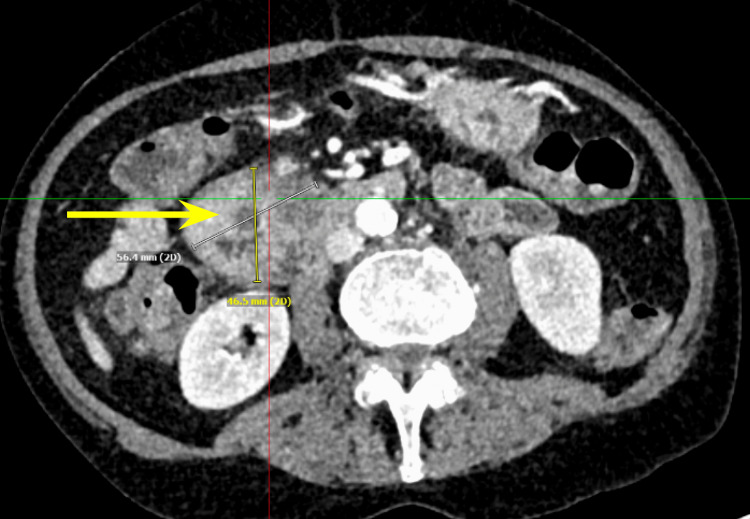

We present a case of a 68-year-old male with a past medical history of prostate cancer requiring radical prostatectomy, hypertension, hyperlipidemia, alcohol use disorder, and 50-pack-year smoking history who presented with several weeks of anorexia, dyspnea on exertion, generalized weakness, nausea, and vomiting. He also noted an unintentional 20-pound weight loss over the last several months. Vital signs were within normal limits with blood pressure of 118/80 mmHg, pulse of 98 beats per minute, respiratory rate of 16 while saturating 100% on room air, and temperature of 98.8°F. Physical exam was remarkable for a cachetic, ill-appearing male in no acute distress. Laboratory evaluation was significant for acute kidney injury (creatinine (Cr) of 2.89 mg/dL from baseline of 0.5-0.6 mg/dL; reference range: 0.51-0.96 mg/d), mild transaminitis with aspartate transferase (AST) of 46 IU/L (reference range: 14-33 IU/L), anion gap of 28 mmol/L (reference range: 4-16 mmol/L), lactic acidosis of 8 mmol/L (reference range: <2 mmol/L), and beta-hydroxybutyrate of 4 mmol/L (reference range: 0.5 mmol/L). CT of the abdomen and pelvis showed three main findings. The first was a large 6.0 cm heterogeneous mass located in the second portion of the duodenum and pancreatic groove (Figures 1–2).